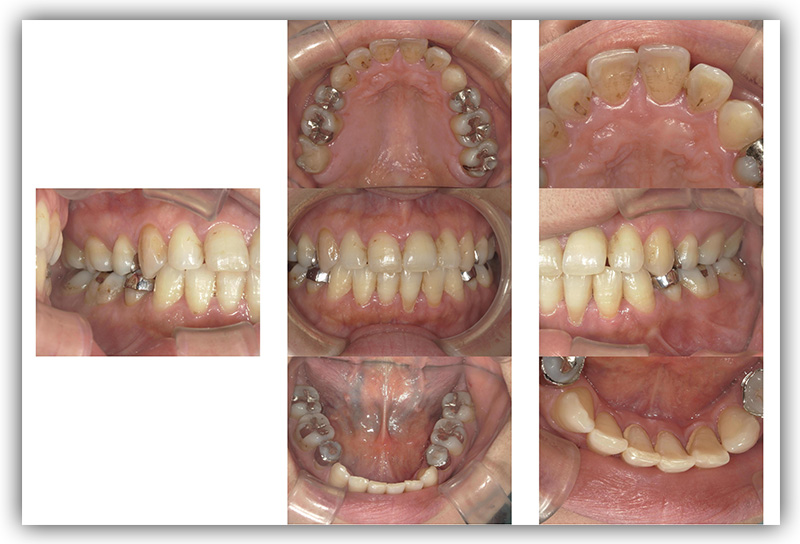

CASE_01

50代女性 セラミック治療(ジルコニア)

- 患者さん情報(年齢・性別)

- 50代 女性

- 主訴

- 銀歯をいれているところをセラミックにしたい。(見た目を良くしたい、今後むし歯になるリスクを減らしたい)

- 治療箇所

- 11箇所

- 治療方法

- セラミック治療(ジルコニア)

- 費用

- 約84万円

- 治療期間

- 約1年6か月